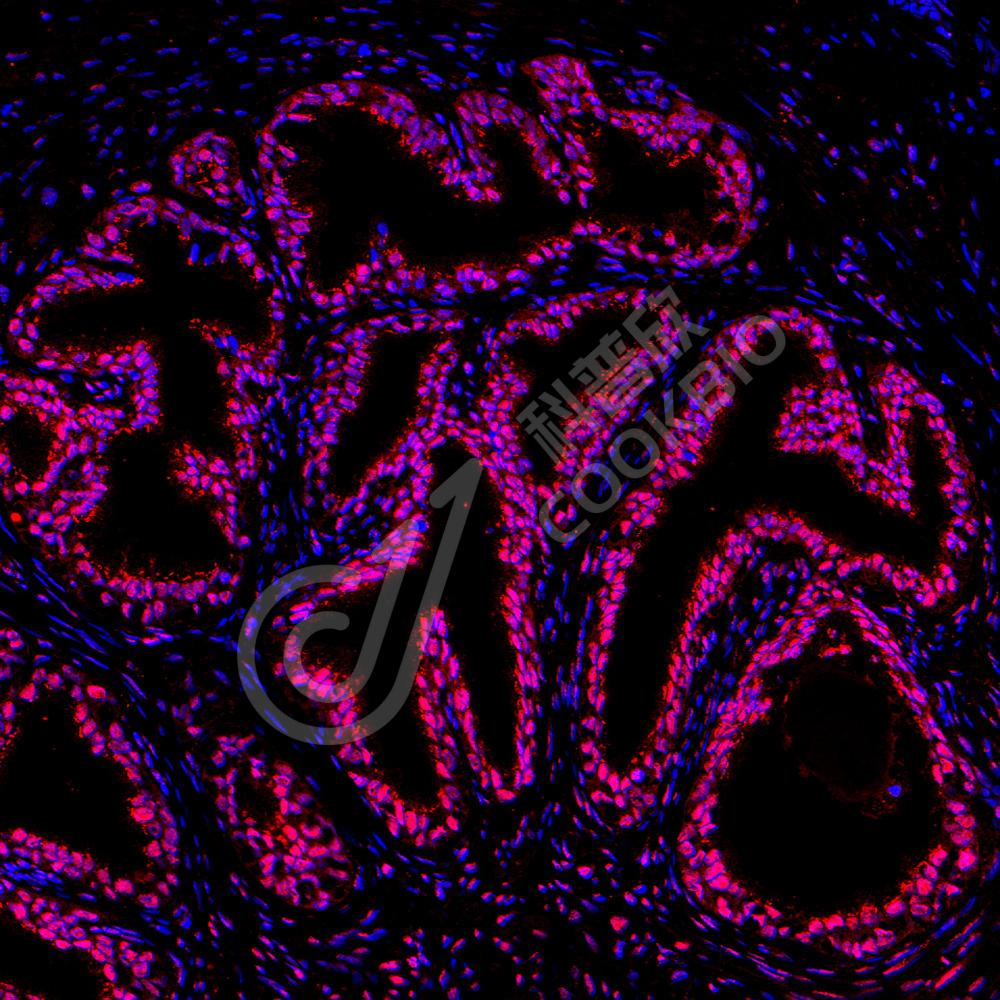

IF检测Nucleolin蛋白(货号 K1336048)(红色).

样品: 人前列腺, 4%多聚甲醛 (货号KSG1101) 固定12-24小时.

抗原修复: Tris-EDTA抗原修复液(pH 9.0) (KSG1203), 98℃, 20分钟.

封闭: 3% BSA(货号KSGC305010)的PBS溶液, 室温孵育30分钟.

—抗: 1: 800稀释, 4℃ 孵育过夜.

二抗: Cy3标记山羊抗兔IgG (H+L) (货号KB63909), 1: 300稀释, 室温孵育1小时.